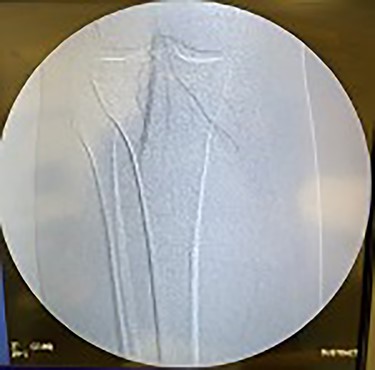

Lastly, the right iliac artery (Fig. 5) was treated using the same method (Fig. 10). After completion of the angioplasty procedure, catheter arteriogram was repeated to visualize the effectiveness of the procedure in relieving the extensive stenosis. The imaging revealed almost complete restoration of the diameter of both left and right iliac arteries (Figs 11 and 12). The distal aorta also showed improved diameter after the procedure (Fig. 9). Angiogram of both lower extremities was also performed. The catheter was passed distal to the stenosis that was previously present in the left iliac artery, to help visualize perfusion of its distal branches (Figs 13 and 14). The catheter was removed from the right femoral artery and reinserted in a distal fashion, to help visualize downstream perfusion. The right popliteal artery was well visualized on angiogram (Fig. 15), signifying strong perfusion. The patient was strongly advised to discontinue smoking cigarettes. In addition, the patient was advised to maintain regular physical exercise as tolerated and take baby aspirin daily to prevent thrombotic events.

Fluoroscopy showing dilation of the distal aorta post-angioplasty.